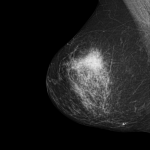

Uma das principais áreas onde a IA tem mostrado grande promessa é no diagnóstico médico. Algoritmos de IA podem analisar grandes volumes de dados, incluindo imagens de exames como tomografias, ressonâncias magnéticas e radiografias, para identificar padrões sutis que podem escapar à detecção humana. Isso pode levar a diagnósticos mais precisos e rápidos, permitindo um tratamento mais eficaz e precoce.

Na imagem abaixo podemos ver como é uma leitura realizada por IA de um exame de mamografia de uma paciente com câncer de mama.